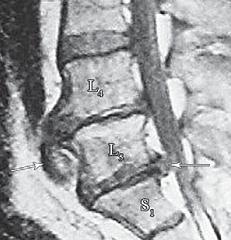

МРТ № 18

На МРТ № 18 наблюдаются грыжи межпозвонковых дисков в сегментах:

— LIV-LV вентральной локализации с образованием каудального секвестра; при расположении межпозвонковой грыжи на один сегмент выше, «конфликт» с брюшной аортой был бы неизбежен;

— LV-SI — дорсальная грыжа межпозвонкового диска, частично компенсированная спондилёзом